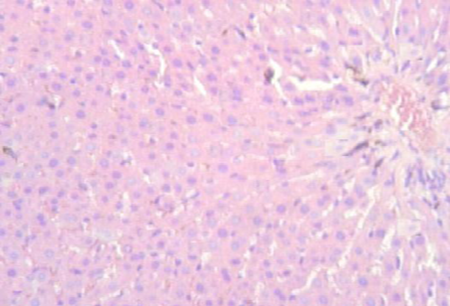

Normal Control:

The liver tissue from the normal control group shows a typical histological structure with well-arranged hepatic cells with clear cytoplasm and well defined nuclei. There are no sign of inflammation, necrosis and celluar damage, indicating healthy liver function.

Figure 1: Normal Control                             Figure 2: Disease Control